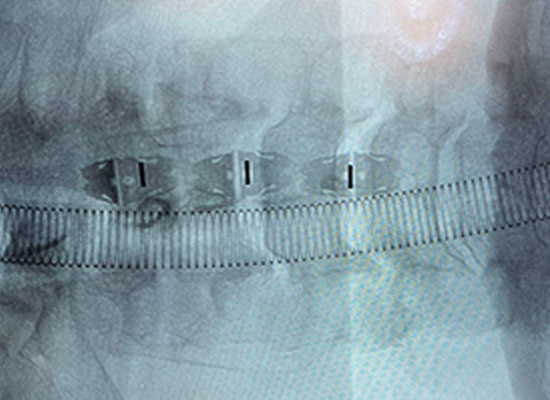

Postoperative Imaging

Postoperative X-ray showing stable fixation and alignment after Uni-C cervical cage implantation in Mexico 1

Postoperative X-ray showing stable fixation and alignment after Uni-C cervical cage implantation in Mexico 2

The patient experienced significant relief of neck pain and left upper extremity radicular pain postoperatively, with gradual resolution of left hand numbness. Follow-up imaging demonstrated stable cage positioning, maintained disc height, and early signs of bone fusion.